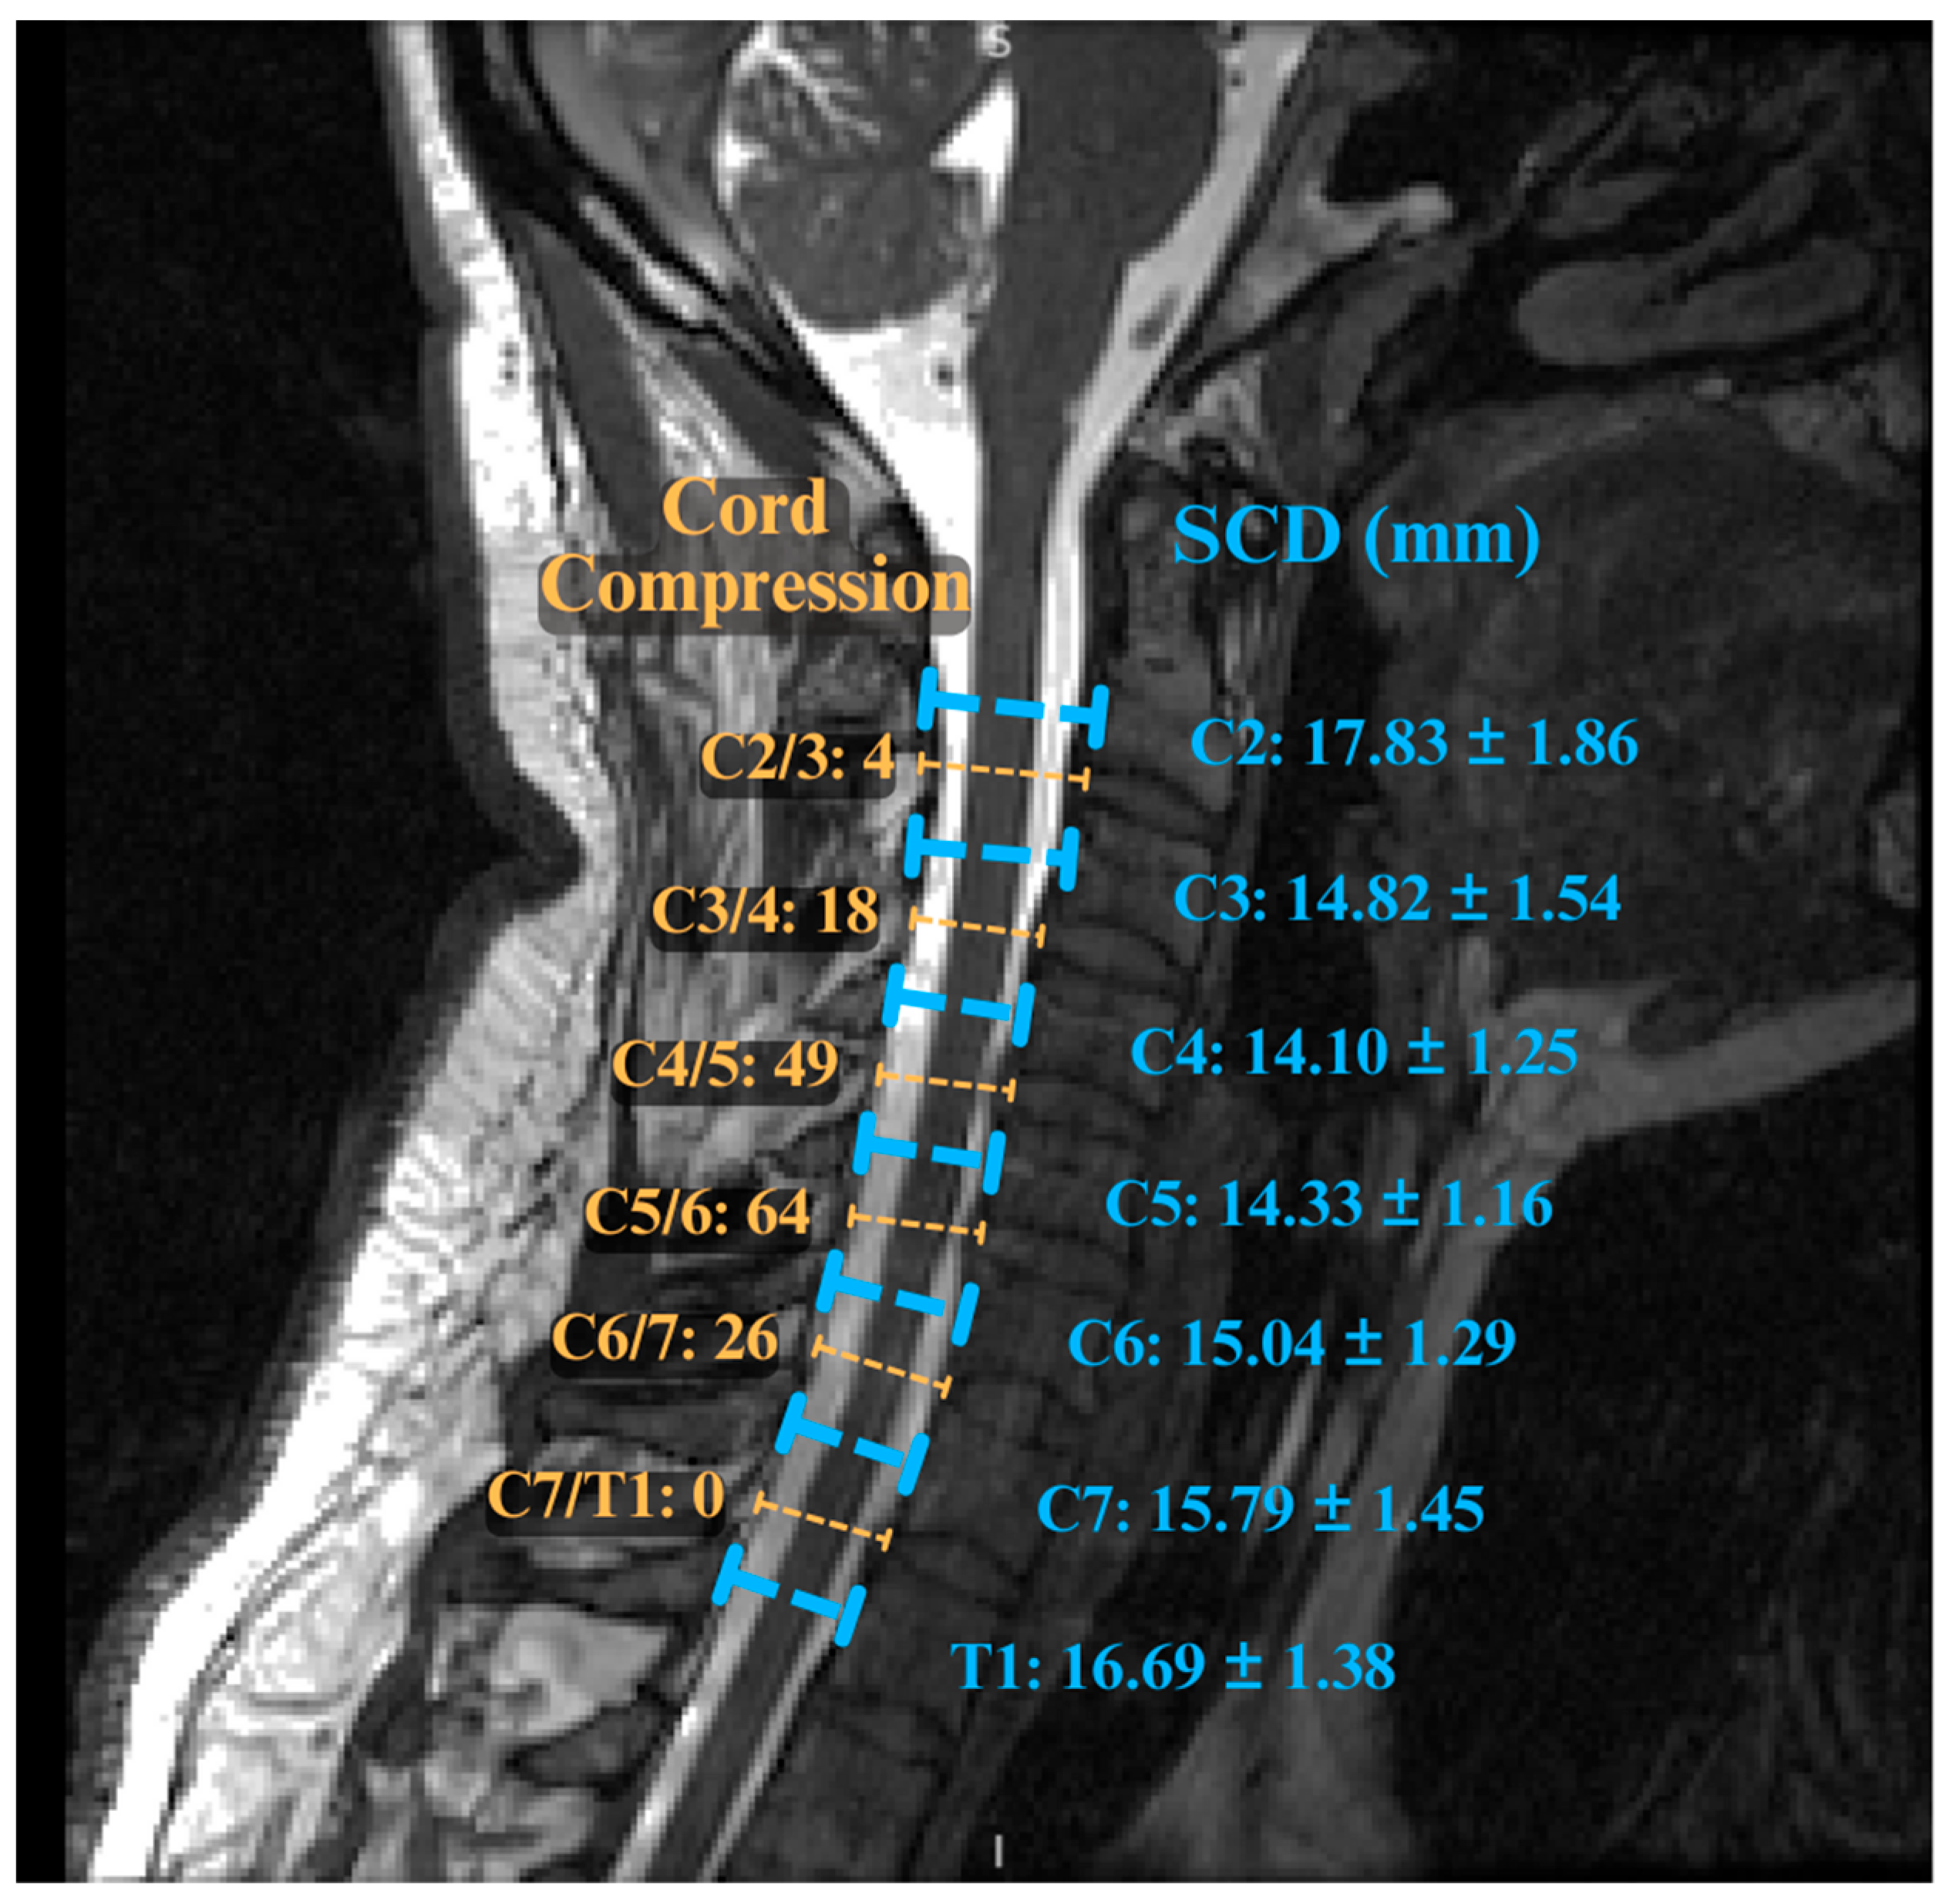

9. Advanced Imaging Markers in DCM